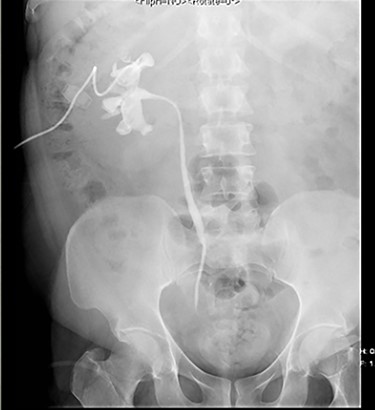

He underwent ureteroscopy and removal of ureteric stent which was inserted 3 weeks ago for an upper ureteric radiolucent stone in another hospital. The patient did not report passing the stone but ureteroscopy was negative. During his recovery after ureteroscopy and stent removal the patient developed right flank pain on Day 1 postoperative and presented to initial hospital, and was discharged from the emergency department on oral analgesics. On the third day he presented to our hospital with anuria and shortness of breath and generalized edema. His laboratory finding showed creatinine level at presentation was 735. Computed tomography (CT) abdomen without contrast showed a subcapsular hematoma with mild hydronephrosis (Fig 1). The patient was taken for percutaneous drainage using 8 Fr nephrostomy tube which drained hematouric urine with clots of 1.5 L (Fig. 2). Post drainage the patient had good urine output and the creatinine level dropped to 492. He was monitored for possible postobstructive diuresis which was anticipated and managed. He recovered his renal functions and creatinine level went back to normal levels with good urine output. On the third day the nephrostomy tube was clamped, and the patient was voiding freely with no flank pain or leak. The nephrostomy tube was removed, and he was discharged. A follow-up CT after 1 month showed complete resolution of the hematoma and the renal profile was normal.

Antegrade pyelogram post drainage and insertion of nephrostomy tube.